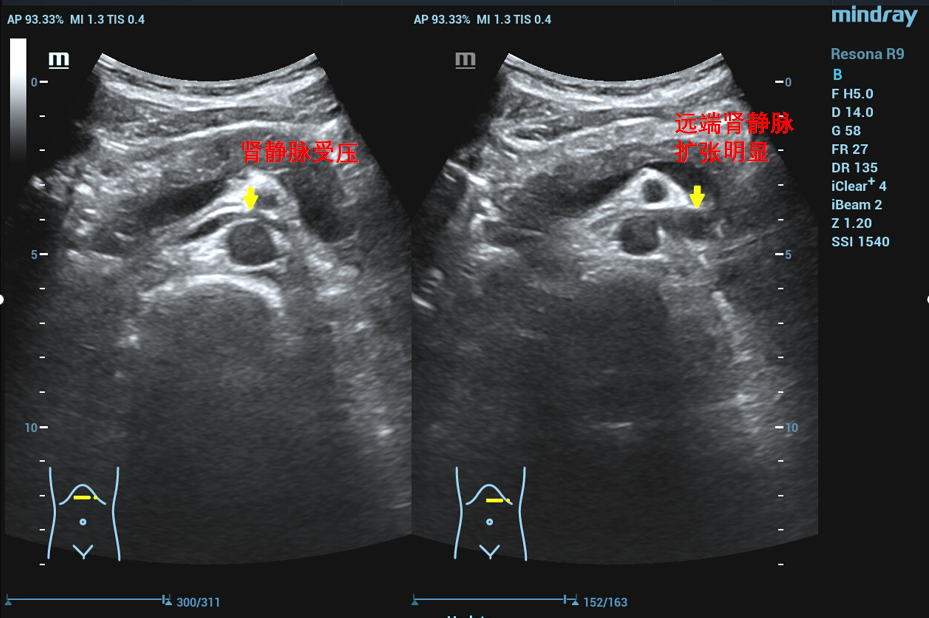

患者于两年前无明显诱因出现肉眼血尿及排尿疼痛,偶有左侧腰部疼痛,无明显精索静脉曲张,曾于基层财神捕鱼 就诊行CT等检查提示左肾静脉压迫综合征,也就是胡桃夹综合征。为进一步的诊治前来财神捕鱼 就诊,经过泌尿外科三病区详细的检查和判断,该患者左肾静脉胡桃夹现象比较明显,临床症状比较重。泌尿外科三病区对患者的病情进行反复的讨论,并与患者的家属和患者本人充分沟通后决定行手术治疗。

在泌尿外科三病区柯昌兴主任、杨博伟副主任医师、李宇航博士团队的精心准备和密切配合下,顺利为患者完成“腹腔镜(3D)下左肾静脉外支架置入术”。术中,见左肾有3根动脉,其中一根动脉绕行并压迫左肾静脉(术前阅片已确认),左肾静脉入肠系膜上动脉与腹主动脉夹角处,其周围纤维条索较多,此处左肾静脉明显变窄,离断纤维条索后此处左肾静脉明显增宽,充分游离左肾静脉近端至下腔静脉,远端至“其中一根动脉绕行并压迫左肾静脉”处,离断左性腺静脉和肾上腺中央静脉。柯昌兴主任团队成功放置一根6cm长带外支撑环的人工血管固定在患者左肾静脉外面,为受压的左肾静脉支撑起一条“生命通道”,提供持久的支撑力对抗肠系膜上动脉和腹主动脉的压迫。整个手术非常顺利,耗时约3小时,出血约10毫升。术后3天,患者康复出院,且腰痛、血尿等术前临床症状明显缓解,手术效果非常显著。